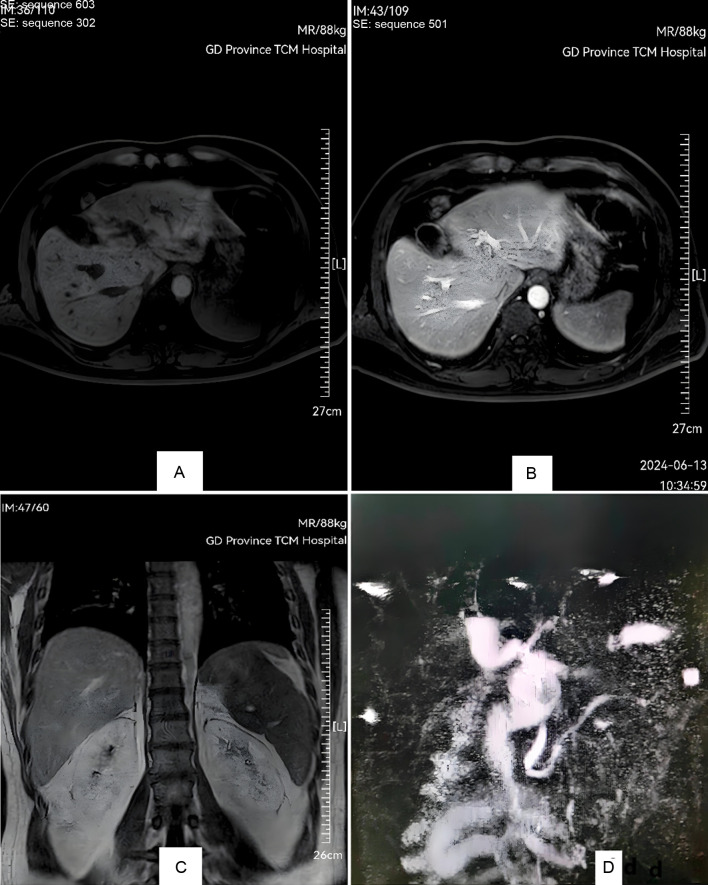

Glucagon-like peptide-1 (GLP-1) and glucose-dependent insulinotropic polypeptide (GIP) receptor agonists are increasingly used in the management of type 2 diabetes mellitus and obesity due to their ability to stimulate insulin secretion, delay gastric emptying, and suppress appetite. The combination of GLP-1 and GIP agonists improves glycemic control and promotes weight loss. However, the introduction of these novel therapies has raised safety concerns, including the risk of cholestatic hepatitis. We report a case of a patient with obesity who was prescribed a GLP-1/GIP dual-receptor agonist as part of his treatment regimen. Importantly, both before the initiation of this therapy and during the course of treatment, the patient was not taking any other medications. Shortly after receiving four doses of the therapy, the patient developed symptoms of severe cholestatic hepatitis, including jaundice and elevated liver enzyme levels. During hospitalization, no alternative causes for the condition were identified, and a liver biopsy confirmed the diagnosis of drug-induced cholestatic hepatitis. This is the first recorded case of cholestatic hepatitis induced by a GLP-1/GIP dual agonist, and it aimed to raise global awareness of this potential side effect.

Abstract Image